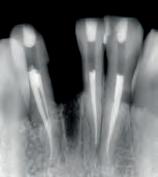

Other types of stains can penetrate into enamel and dentin from the inside, as a consequence of diseases, injury or medical treatment, e.g. congenital, systemic, metabolic, pharmacological, traumatic, or iatrogenic factors such as dental fluorosis, jaundice, tetracycline, and adult minocy-cline stains, porphyria, trauma, and erythroblastosis fetalis. To treat staining from these causes, a medical, in-office whitening system is needed. In many cases such focused whitening may make restorations, veneers or crowns unnecessary or postpone them for a long time.

Opalescence whitening gel is recommended for whitening discolored teeth prior to placement of composite, veneers, and/or crowns. It is effective in breaking down some or all internal tooth discolorations due to factors such as congenital, systemic, pharmacologic, traumatic, etc., as well as aging. It is successful with staining from fluorosis and tetracycline.3,6